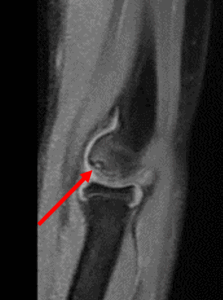

・MRI検査:骨、軟骨損傷や靱帯損傷の有無・範囲などを詳しく検査

・上腕骨小頭離断性骨軟骨炎